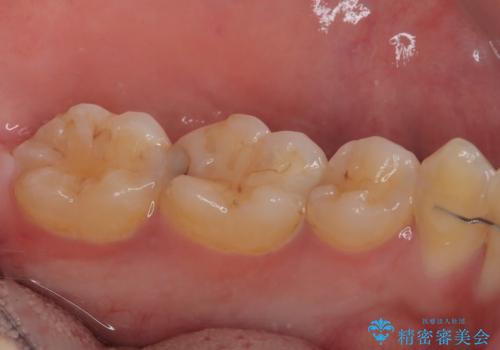

- 当院で矯正治療を終えて、左下が虫歯になっている気がするとのことで来院された患者様です。レントゲン検査の結果、コンポジットレジンによる修復箇所が複数行われており、詰め物の下に虫歯を認めました。

拡大鏡視野下でコンポジットレジン、虫歯の除去を行い、オールセラミッククラウンに適した形に整えました。